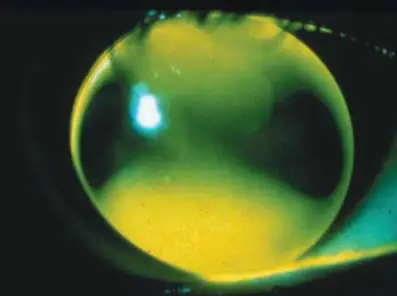

本題四張螢光圖(fluorescein pattern)均以鈷藍光(cobalt blue light)配合黃色濾鏡拍攝,螢光素亮綠色代表淚液積聚(pooling/clearance),暗色(黑色或深色)代表鏡片貼觸角膜(bearing/touch)。

(A) 選項圖:中央區呈現深暗色(dark),代表鏡片中央緊貼角膜(central bearing/touch);中周邊出現一圈較亮的綠環;周邊仍有邊緣翹起(edge lift)。此圖型整體偏過平配戴(flat fit)——中央觸碰、中周邊可能有輕微撐起,螢光呈圓環狀分布。

(B) 選項圖(正確答案):整個光學區呈現均勻、淡而一致的亮綠色(light even green);中央、中周邊、周邊均有薄而均勻的淚液膜,沒有